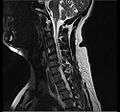

MRI scan of large herniation (on the right) of the disc between the L4-L5 vertebrae.

MRI Scan of lumbar disc herniation between fourth and fifth lumbar vertebral bodies.

A rather severe herniation of the L4-L5 disc.

Example of a herniated disc at the L5-S1 in the lumbar spine.